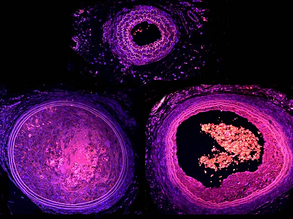

Vessel Makers